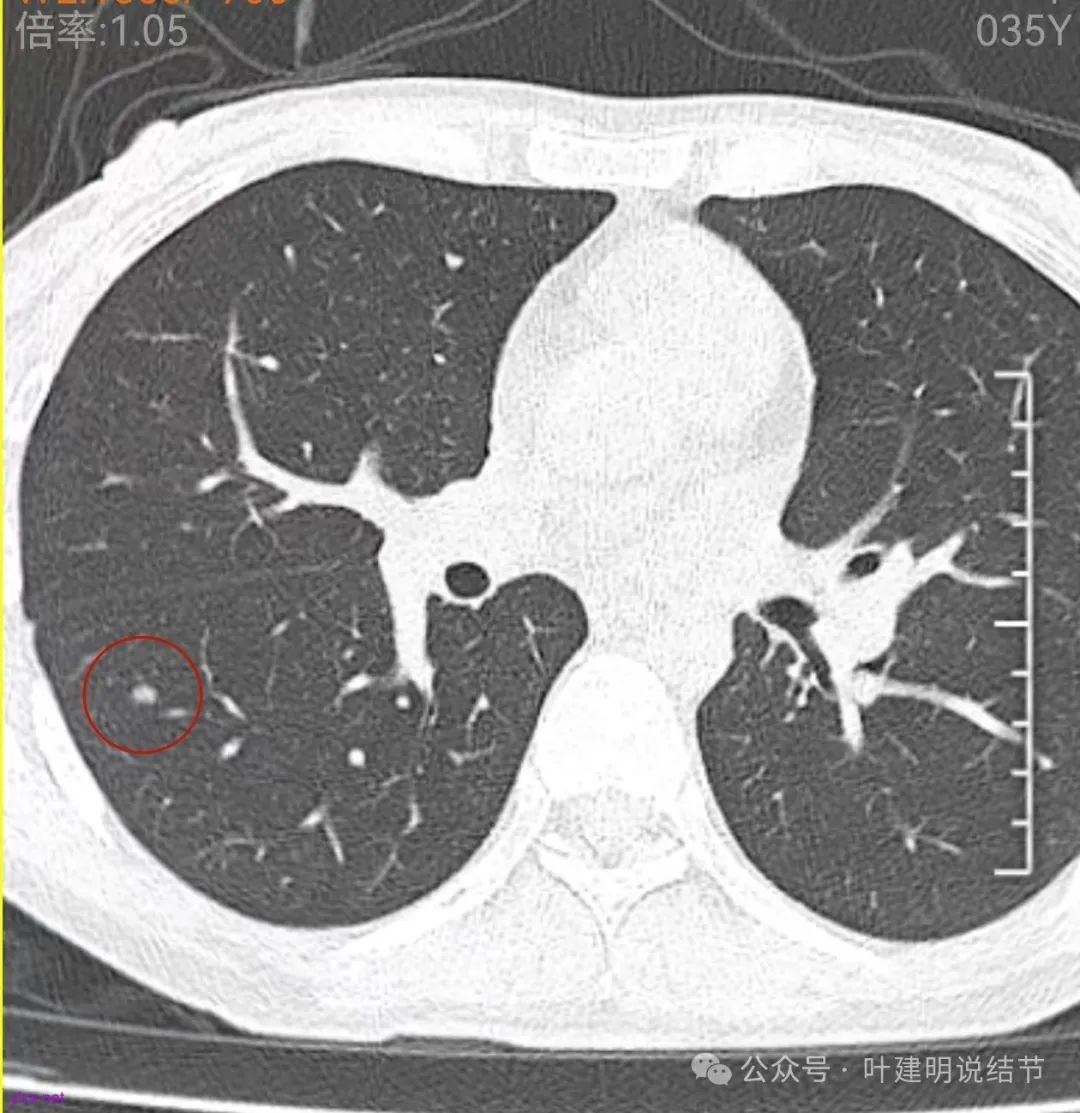

再看中间2023年的影像:

右下此灶2023年时此层面淡而边显糊。

上图层面已经像混合密度了,表面毛糙不光滑,灶内密度不均,也有小空泡征的样子。

感觉这处(在上截图结节的下面点,邻近层面)不像前面病灶的延伸,否则这密度的变化有点突兀呀。